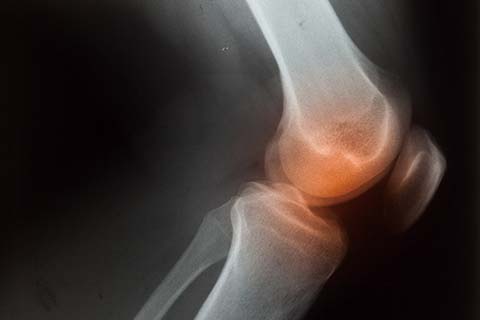

• 퇴행성관절염

노화로 인해 관절 연골이 손상된 질환입니다.

퇴행성관절염 치료방법

• 비수술적 치료 약물치료, 주사치료, 유전자세포치료제

• 수술적 치료 근위경골절골술, 무릎 관절경 수술, 무릎 인공관절 치환술